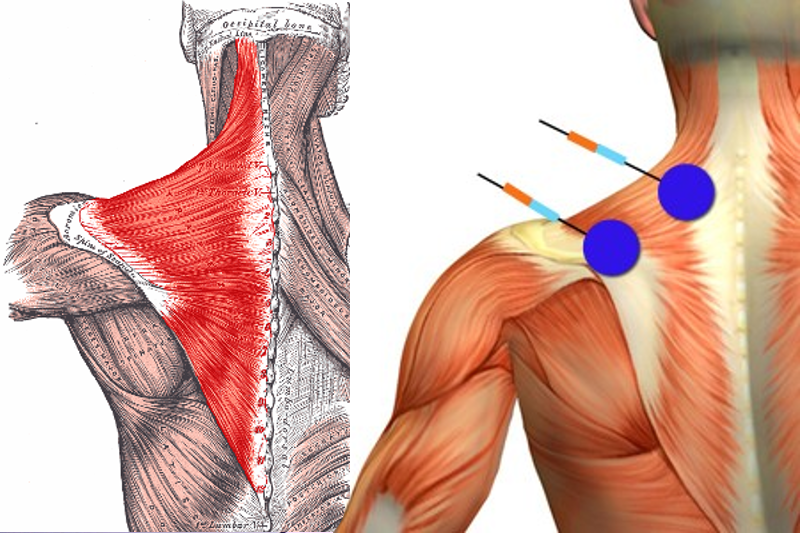

Read MoreWhat is Trapezitis & How is it Treated?

What is Trapezitis? Trapezitis is an inflammation caused in the trapezius muscles which further leads to pain and spasm in the neck. It is increasingly becoming common among people working at desk, using computers and also those who do physical labor or use their neck and back muscles a lot. It is necessary to know […]

Read MoreCHRONIC CERVICAL MYOFASCIAL SYNDROME

BACKGROUND Pain attributed to muscle and its surrounding fascia is termed myofascial pain, with cervical myofascial pain thought to occur following either overuse or trauma to the muscles that support the shoulders and neck. In the cervical spine, the muscles most often implicated in myofascial pain are the trapezius, levator scapulae, rhomboids, supraspinatus, and infraspinatus. […]